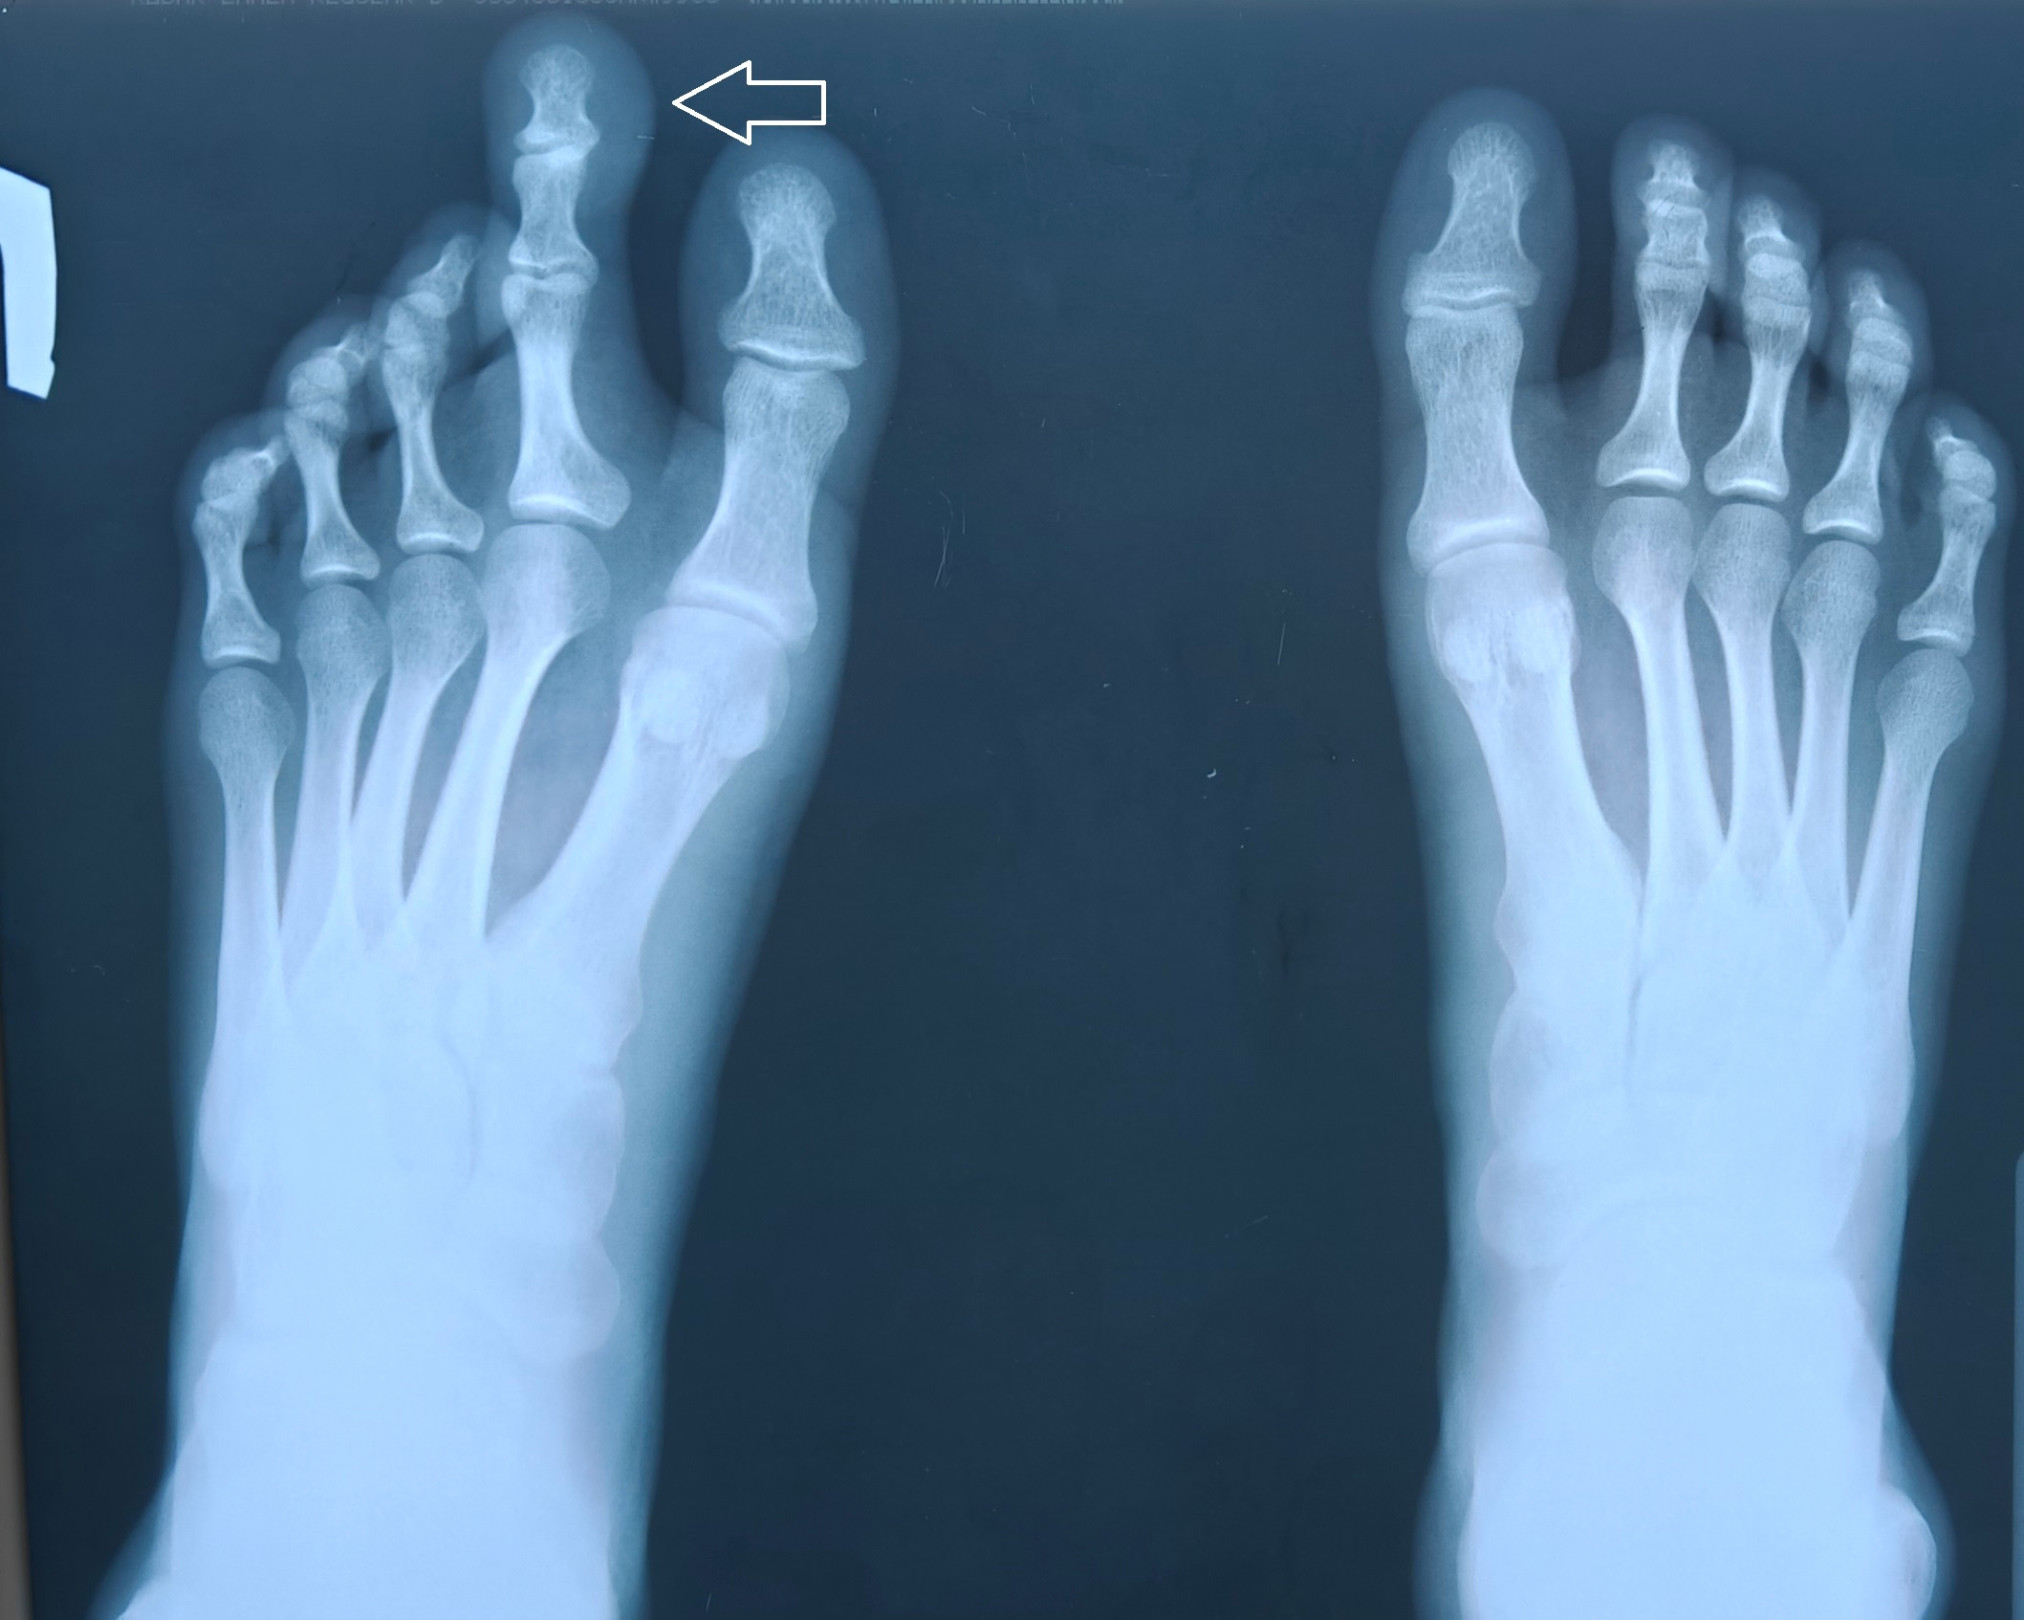

На консультативный прием к специалисту медучреждения обратились 17-летняя девушка со значительным увеличением II пальца левой стопы. Это стало следствием редкой врожденной аномалии развития.

Парциальный гигантизм (синдром Протея) — редкое врождённое заболевание, при котором увеличивается определённая часть тела (гипертрофируются мягкотканные и костные структуры). Чаще всего патология врождённая, но схожие клинические проявления могут иметь и приобретённый характер, например, после нейроинфекций. Частота: менее 1 случая на 1 миллион населения. Чаще всего в патологический процесс вовлекаются пальцы стопы или кисти. При рождении признаки заболевания отсутствуют, симптомы обычно появляются на первом-втором году жизни.

Девушка с гигантским пальцем на ноге жаловалась на то, что стопа выглядит некрасиво, и что ей трудно подобрать себе обувь. Травматологом-ортопедом было назначено оперативное вмешательство с целью коррекции аномалии. Операцию провели врачи отделения травматологии и ортопедии №1.